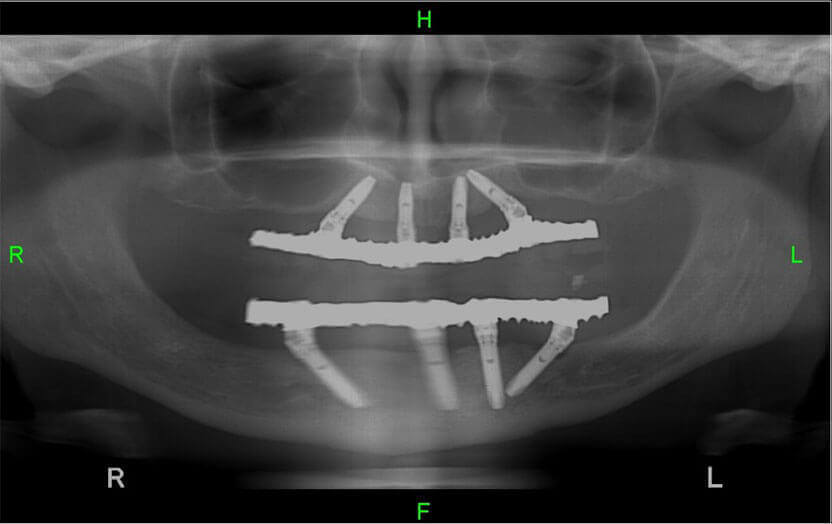

לדוגמא: ניתן לראות זאת בצילום הבא המציג מטופל שהורכבה לו מערכת השיניים בשיטת 'אול און 4' בלסת העליונה ובלסת התחתונה:

השתלת שיניים על גבי 4 שתלים - All on 4